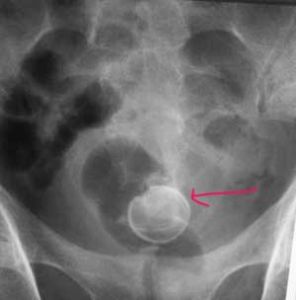

姜洪波,男,副主任醫師,副教授。擅長運用腎鏡、輸尿管鏡及氣壓彈道碎石技術治療泌尿系統結石。